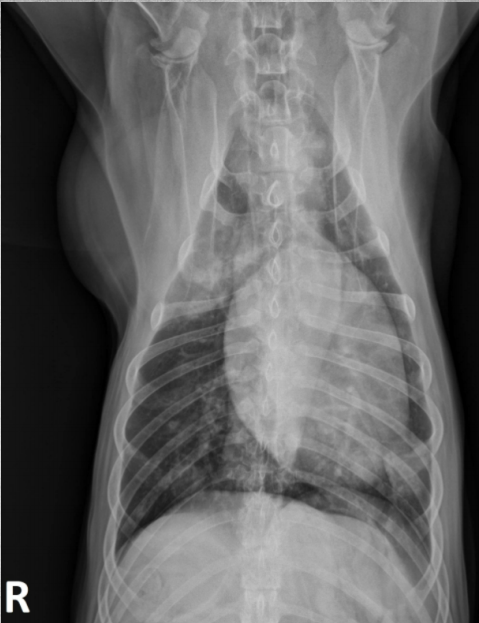

● Female feral cat

● Respiratory distress after handling

diaphragmatic hernia + pregnancy before day 45